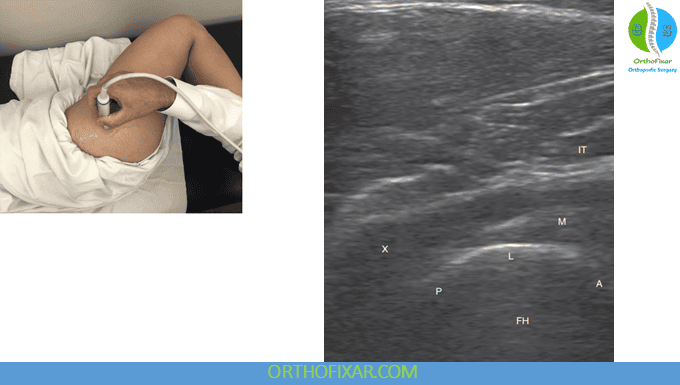

The posterior hip region contains key structures such as the sacroiliac joint and the piriformis muscle—often implicated in buttock pain.

- Begin with a short-axis view over the sacral foramina and sacroiliac joint.

- The superior SI joint appears wider; the inferior portion is narrower.

- Move the transducer obliquely laterally toward the greater trochanter.

- Piriformis muscle in its long axis

- Piriformis tendon, lying just above the bony contour of the ilium

By rotating the patient’s hip, passive movement of the piriformis tendon can be observed—helpful in diagnosing piriformis syndrome and related neuropathies.